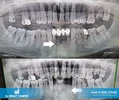

السن المطمور - ماذا يعني السن المطمور؟ يُطلق على الأسنان التي لم تستطع أخذ مكانها في الفم بالرغم من حلول وقت بزوغها لعدة أسباب مختلفة "الأسنان المطمورة". الأضراس الثالثة الكبيرة (المعروفة أيضاً بأسنان العقل أو أضراس العشرين)، هي أكثر الأسنان المطمورة شيوعاً.

الأسنان المطمورة